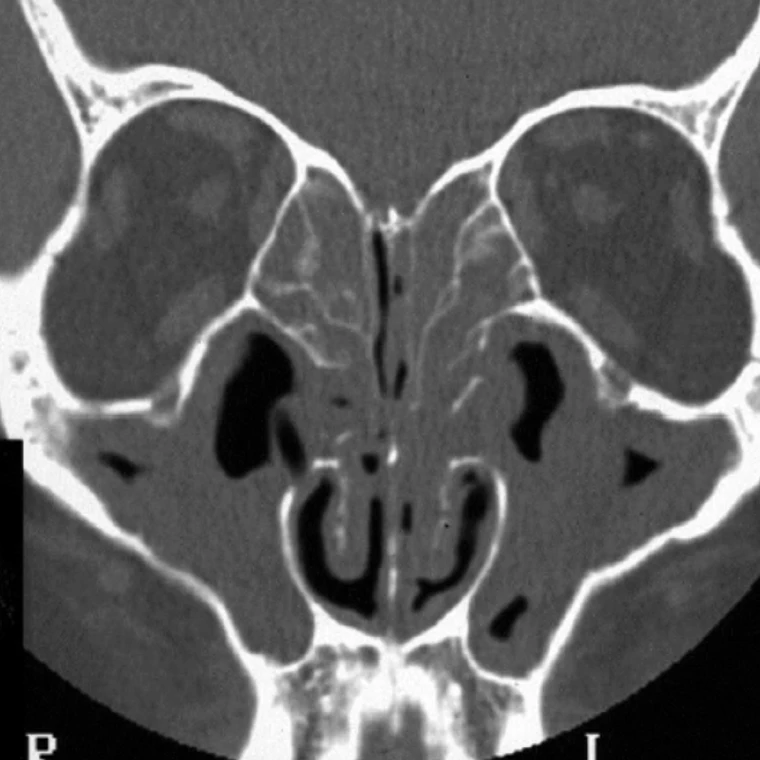

- Pathologies sinusiennes non traités :

– Inflammatoires (polypose, allergie, maladie systémique)

– Infectieuses (bactérienne ou fungique)

– Tumorales (maligne ou bénigne) - Patient immunodéprimé, diabétique…

Les différentes études cliniques ne retrouvent pas d’augmentation significative des pathologies sinusiennes suite à la pose d’implant intra-sinusien.

La pose d’implant intra-sinusien est possible chez tous les patients asymptomatiques, sans antécédent de pathologie sinusienne, avec un bilan d’imagerie des sinus normal.

Un avis ORL sera demandé avant la pose d’implant intra-sinusien, pour les patients ayant des antécédents de pathologie sinusienne ou des symptômes sinusiens (nez bouché, écoulement nasal, perte de l’odorat, douleurs, éternuement).

Un scanner sinusien anormal contre-indique la pose d’implant.